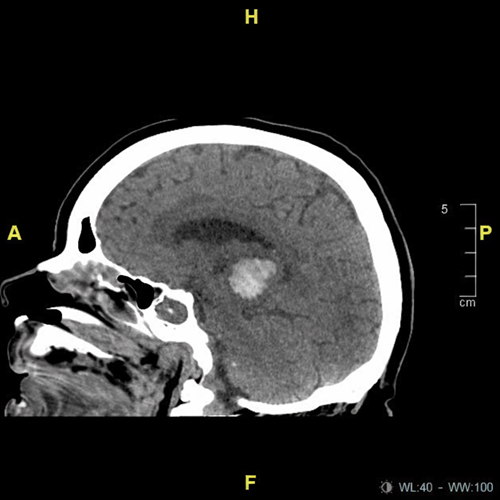

Tomografía de cráneo

- Hemorragia intraparenquimatosa talámica izquierda

- ICH score: 1 punto

- Evento vascular cerebral hemorrágico (hemorragia talámica izquierda)

Se trata de un caso clásico de hemorragia intracerebral hipertensiva, secundaria a daño crónico de arterias perforantes profundas. La localización talámica explica la combinación de alteraciones motoras y del estado de alerta.